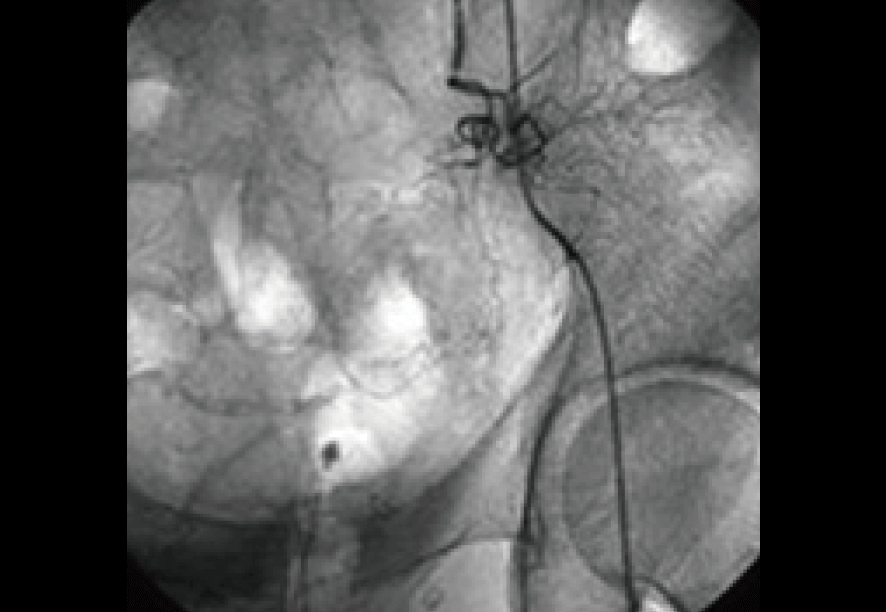

その結果著しいがんの活動性は治療開始3ヶ月で消失、腫瘍も急速な縮小を認めた。

こうして治療を十分に行う時間的余裕を確保した上で、さらに体内からのがん細胞排除を目的としたサイトカイン誘導治療をしばらく継続する方針がとられることになった。

治療後の調査画像。治療前に存在したがんの新生血管は消失し、がんも見当たらない。